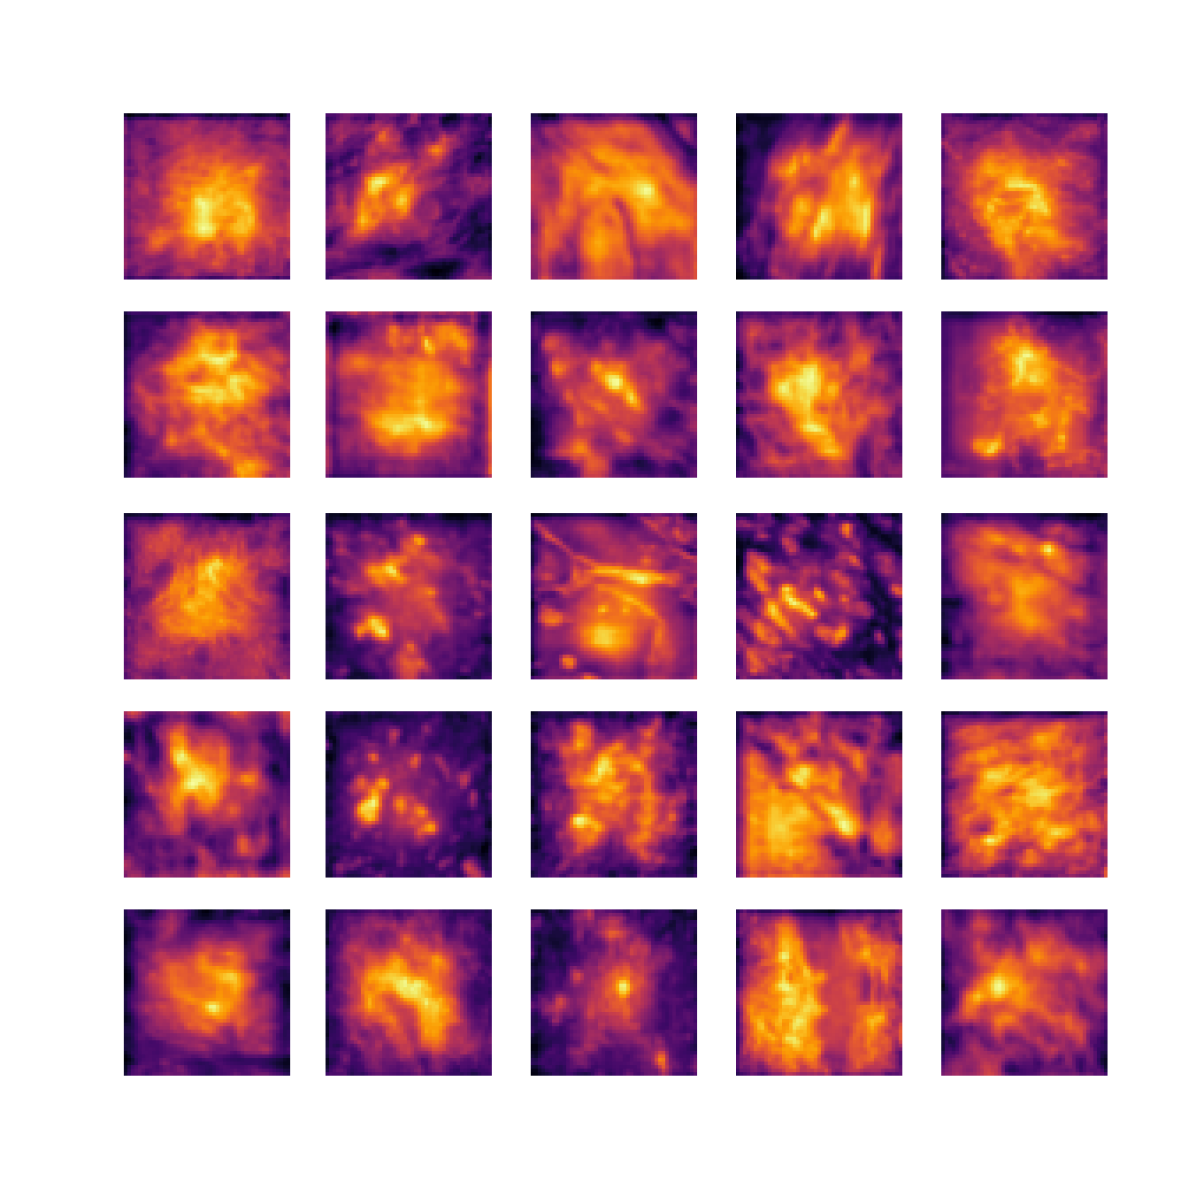

We also analyse the activation maps for each model using GradCAM as described in section S3. This offers more insight into the areas of the image which are contributing most heavily to the models’ representations. In Figure 4(b) we present some representative examples, however, a larger selection which was chosen at random is presented in Figures S10 to S25. The larger selection makes it easier to see the emergent patterns, including that privileged Siamese models tend to mainly identify features which are strongly present in both inputs, while unprivileged Siamese models tend to learn more diffuse features that are not specific to one cell phenotype or image region. TriDeNT ♆ incorporates both sets of features, learning both features specific to the privileged data and more the general features associated with unprivileged Siamese networks.

We can see in Figure 4(b) panel A that for ERG, the privileged Siamese model focuses almost exclusively on any nuclei which could be endothelial cells. As there are very few endothelial cells in the dataset, it could be an effective strategy to identify anything that could potentially be an endothelial cell to minimise the difference between the representations of the H&E model and the IF mask model. In the corresponding unprivileged Siamese image, we see that the model identifies some of these nuclei, albeit less strongly, but also focuses heavily on the other tissue and even the background, while strongly fixating on two spots of debris in the center of the image. This model has less ‘incentive’ to learn the weak features related to endothelial cells as these occur rarely and are not easy to detect, while more generic strong features such as the presence of connective tissue and the prevalence of background are more common and predictable from augmented images. We see that TriDeNT ♆ combines these two feature sets, strongly identifying nuclei while also identifying the connective tissue.

In panel C we see a similar pattern, with the privileged Siamese model fixating solely on the nuclei, while the TriDeNT ♆ model takes a more balanced approach. The unprivileged Siamese model appears to focus on a single cluster of nuclei while neglecting others, and similarly identifies an area of fibroblasts with its distinctive pattern but does not others.

In contrast to panels A and C which represent models with poor privileged Siamese results, panels B and D represent models whose privileged Siamese results were comparable to both TriDeNT ♆ and even the supervised baseline. It is therefore interesting to note that there are far more similarities between the privileged Siamese and TriDeNT ♆ models in both cases. Particularly in panel B, TriDeNT ♆ and the privileged Siamese model return virtually identical heatmaps, with both strongly identifying epithelial nuclei and neglecting the same areas of connective tissue. The unprivileged model in this case appears to focus solely on the centre of the image, giving a significantly different heatmap to the other panels.

Panel D again shows the previous pattern, with the privileged Siamese model identifying the features strongly present in the privileged data – fibroblasts – while neglecting the nuclei present. TriDeNT ♆ also strongly identifies the connective tissue, but, unlike the privileged Siamese model, does not completely neglect the nuclei. The unprivileged Siamese model primarily identifies background, and does not appear to identify the nuclei in this example.